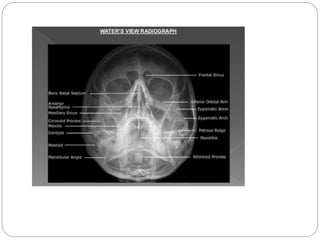

FACIAL BONES

• LATERAL PROJECTION • PARIETO-ACANTHAL PROJECTION

(WATER’S)

 PA AXIAL PROJECTION- CALDWELL

 PARIETOCANTHAL PROJECTION- WATER’S

for maxillary sinuses

 • PARIETOCANTHAL PROJECTION – WATER’S

WITH OPEN MOUTH

 For maxillary and ethmoidal sinuses

FACIAL BONES • LATERALPROJECTION • PARIETO-ACANTHAL PROJECTION (WATER’S)

PARANASAL SINUSES  PAAXIAL PROJECTION- CALDWELL  PARIETOCANTHAL PROJECTION- WATER’S for maxillary sinuses  • PARIETOCANTHAL PROJECTION – WATER’S WITH OPEN MOUTH  For maxillary and ethmoidal sinuses